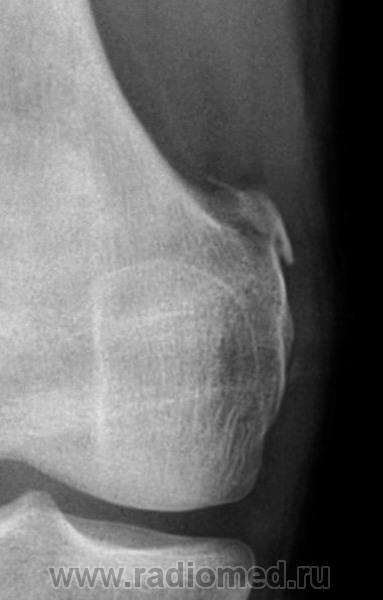

Помянем Штида

Зачем поминать. Лучше вспомнить.

А в диафизе ББК что?

Точно! Не инфаркт ли?

Угу, следствия.